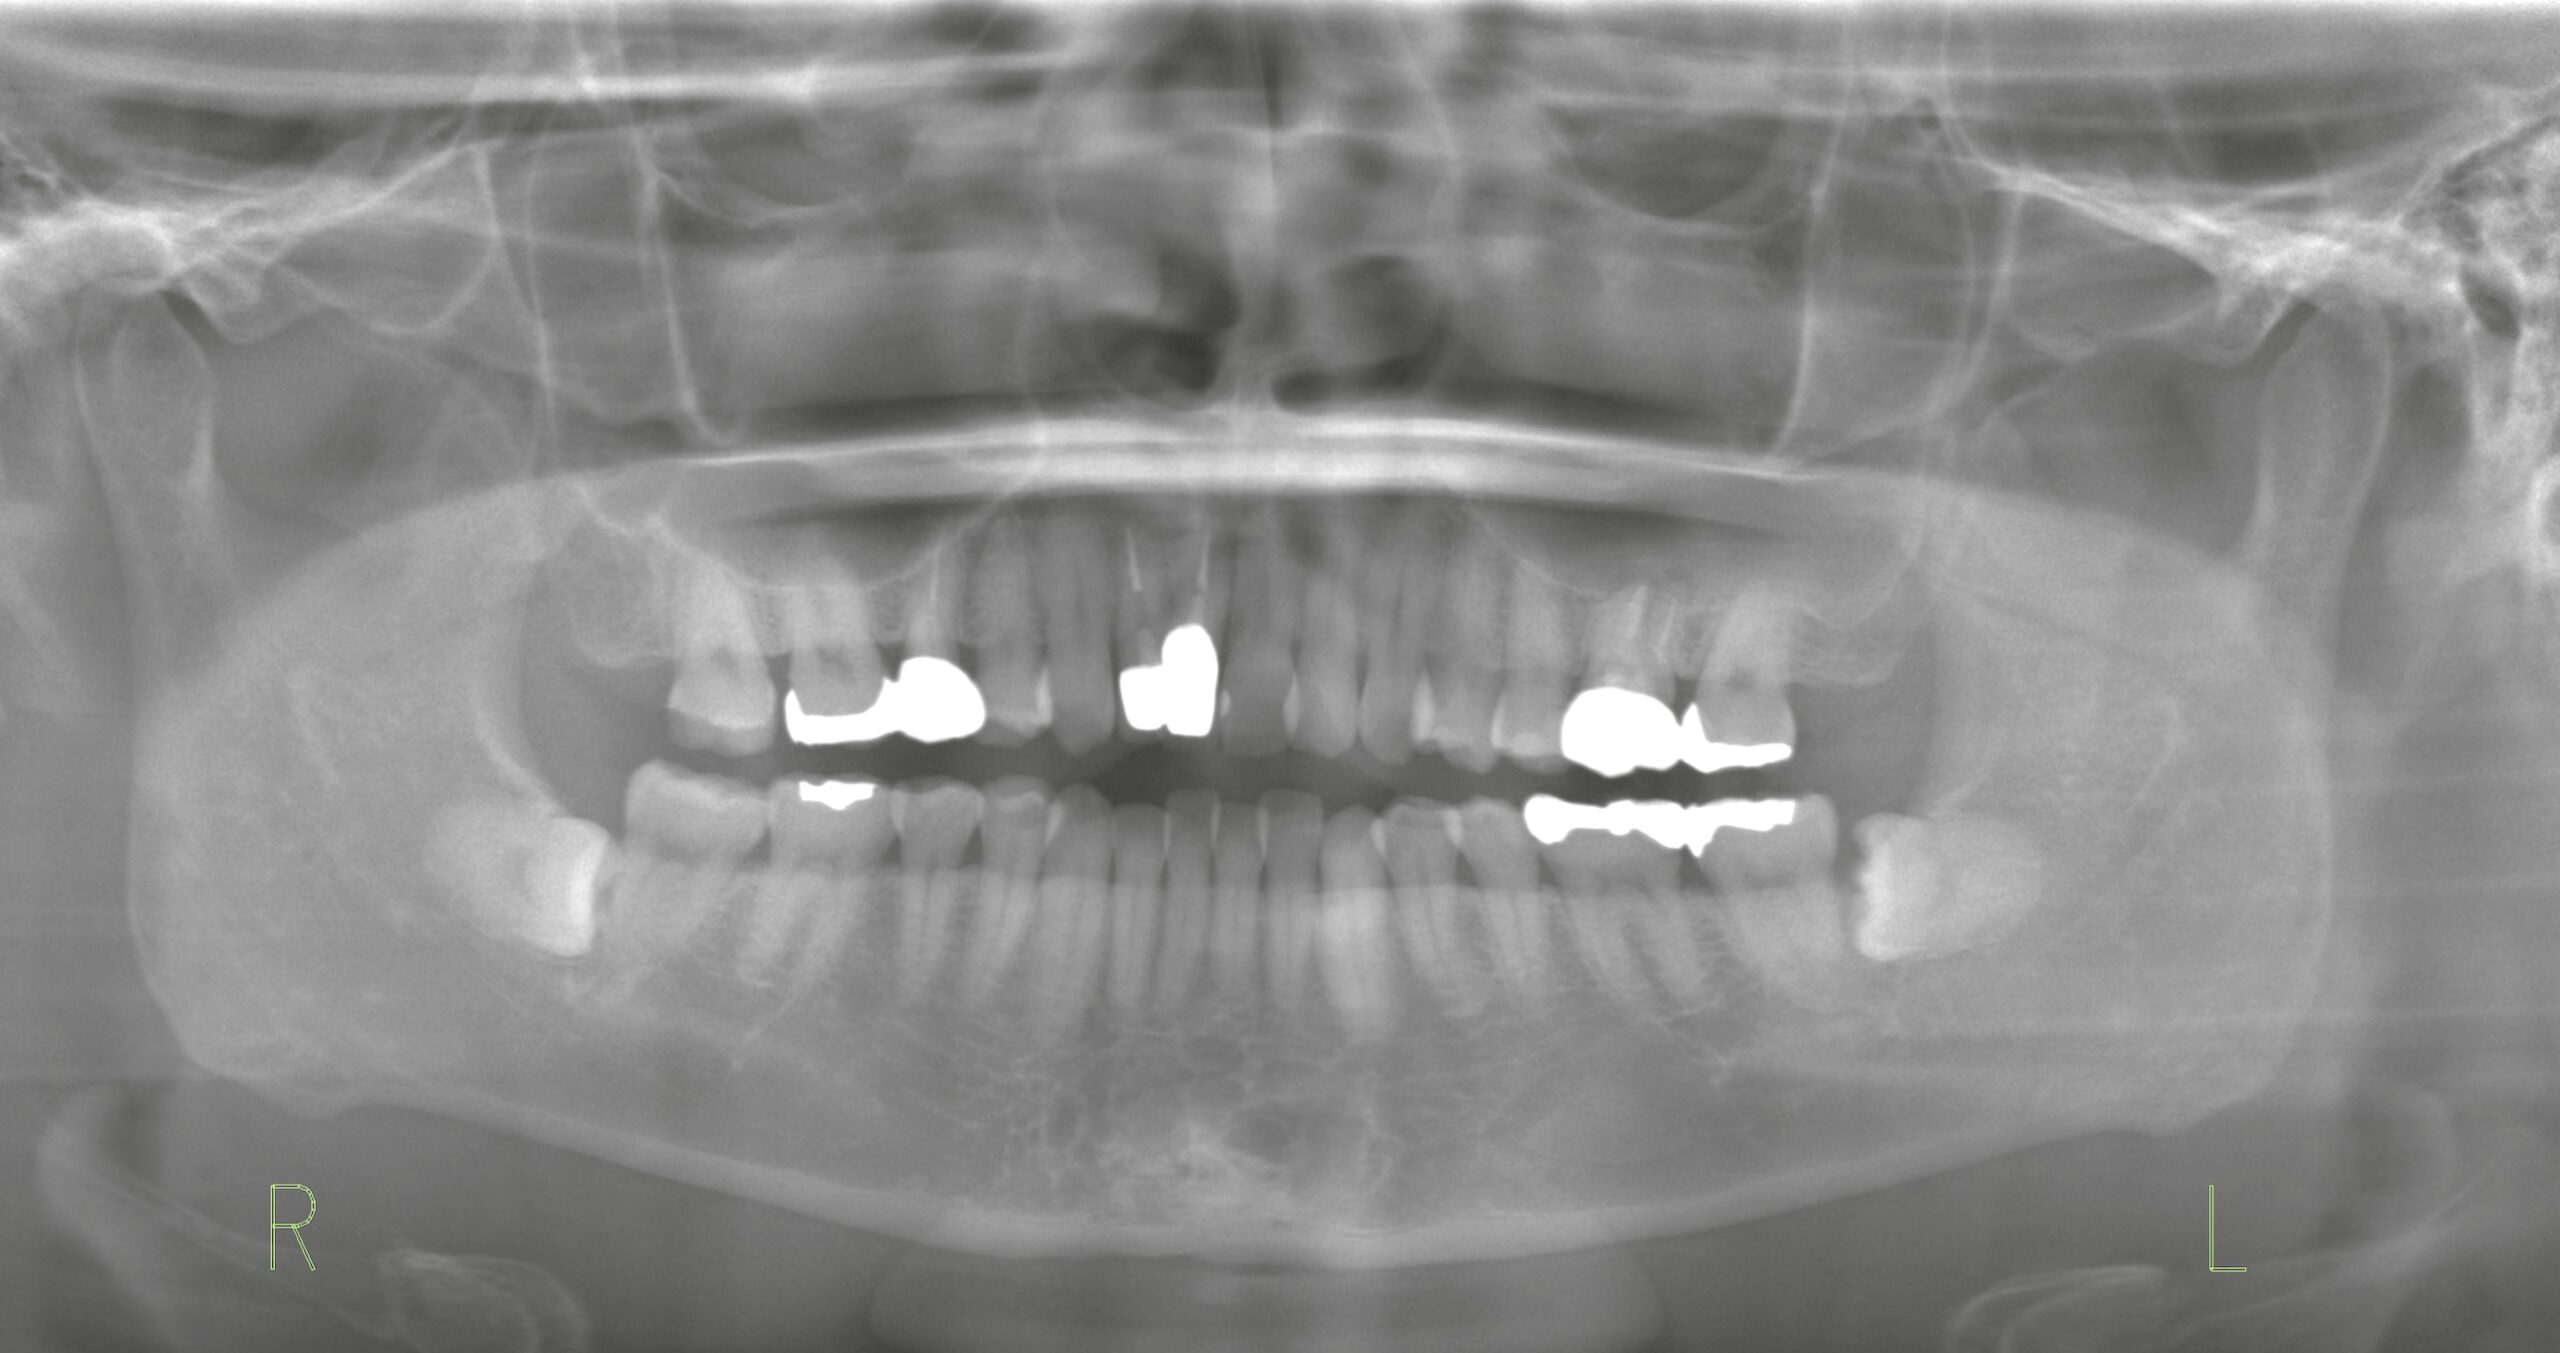

レントゲン所見(パノラマX線)

パノラマレントゲンでは、左右とも下顎の親知らず(智歯)が水平埋伏している状態が確認されました。

* 左下親知らず:第二大臼歯との間にわずかなスペースがあり、細菌が侵入しやすい環境。

* 右下親知らず:水平埋伏しているが、スペースがなく症状も認められない。

このように「親知らずが半分だけ生えている」「スペースがある」という状態は、清掃不良や細菌感染による腫れ(智歯周囲炎)を繰り返しやすくなります。